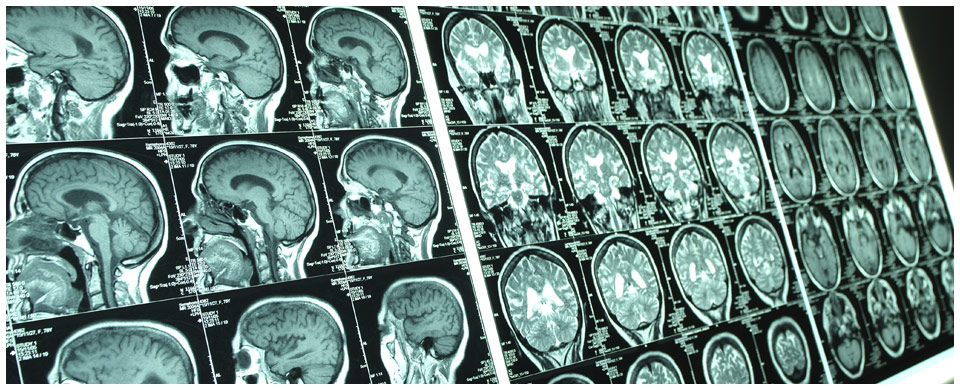

The Nevada Ear + Sinus Institute specializes in the medical and surgical diagnosis and treatment of disorders encompassing the ear, hearing, balance, sinus and allergies.